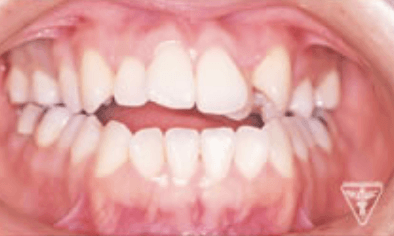

20代女性:オープンバイト(開咬)をゴムメタルにて矯正治療したケース

症状

オープンバイトは、上下の歯を噛み合わせた時に奥歯は噛んでも前歯が噛まない歯列不正の1つです。

原因には遺伝的なものや指しゃぶり 舌癖 口呼吸など様々なものが上げられます。

前歯で噛み切れない、正しく発音しにくいなどの機能障害をはじめ、顎関節症・歯周疾患を併発する可能性があります。

治療前、装置装着直後